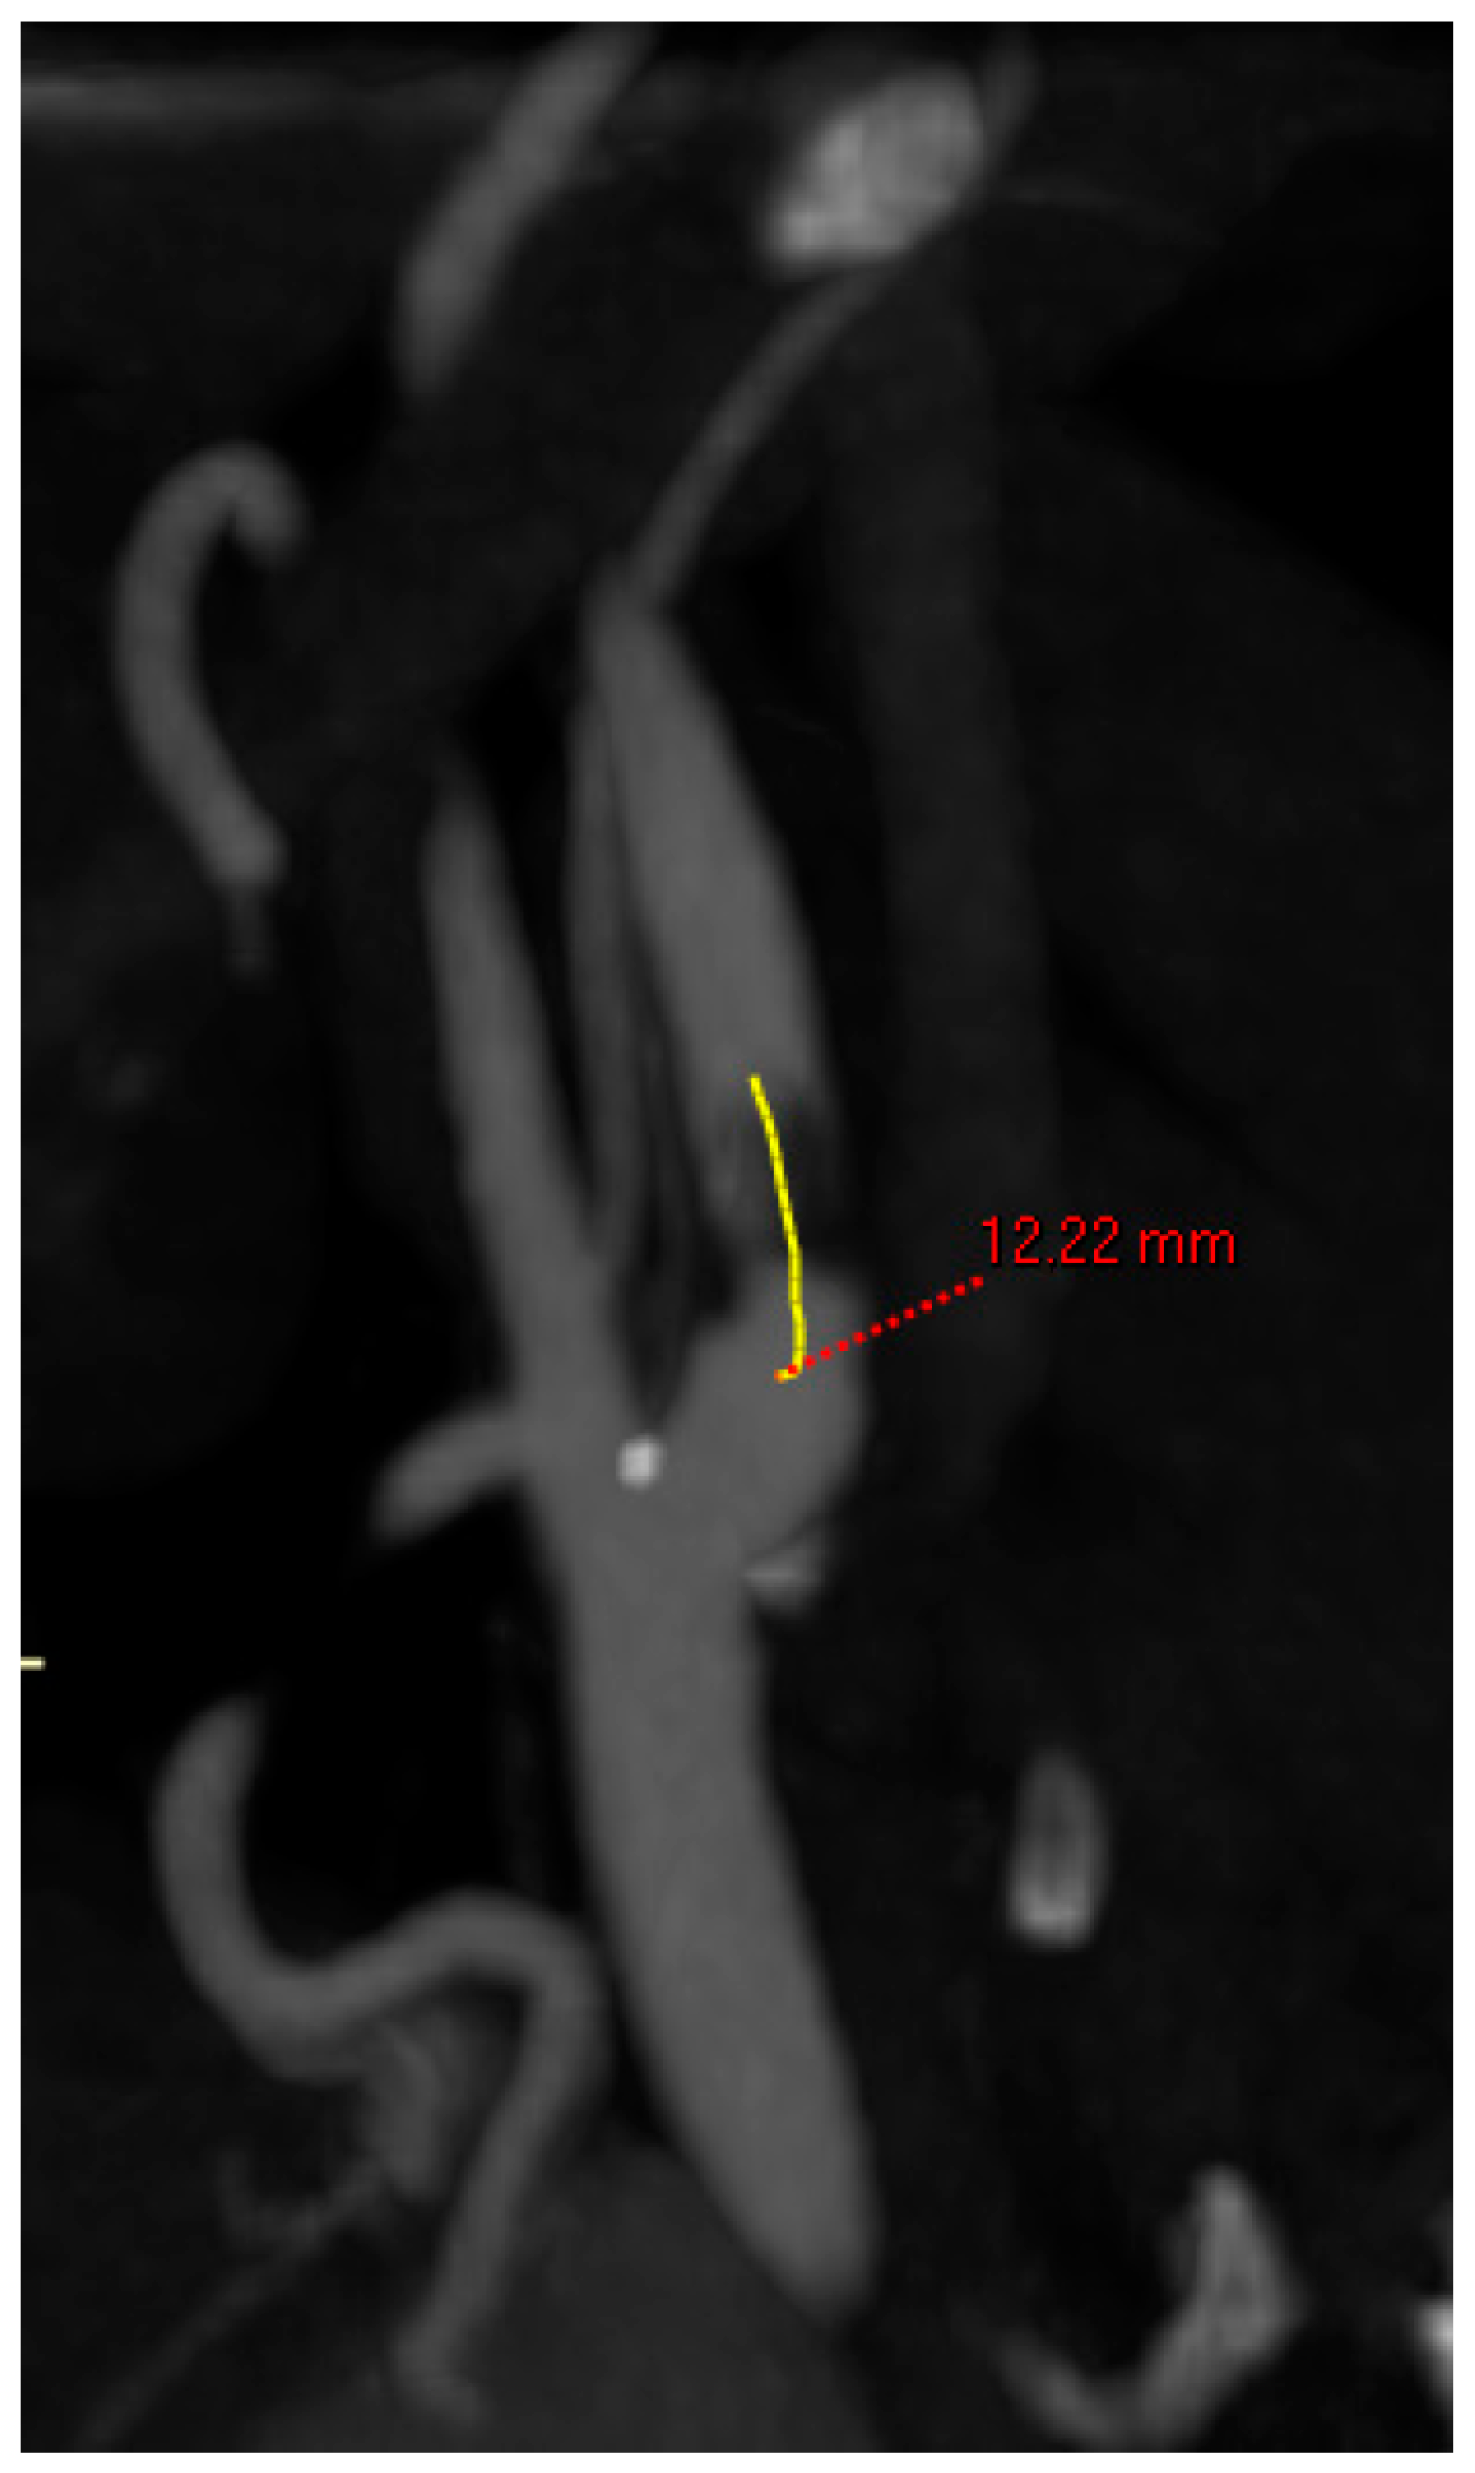

- Length of lesion: centerline measurement in mm of the entire length of the atherosclerotic lesion (Figure 2);

Figure 2. Centerline measurement of the length of the lesion.

The anatomic features are summarized in Table 2. Right-sided lesions were 20% more frequently intervened. The mean degree of stenosis was 81 ± 11%. The mean stenosis length was 25 mm. The mean diameter of the CCA was 7 mm and of the ICA was 5 mm.